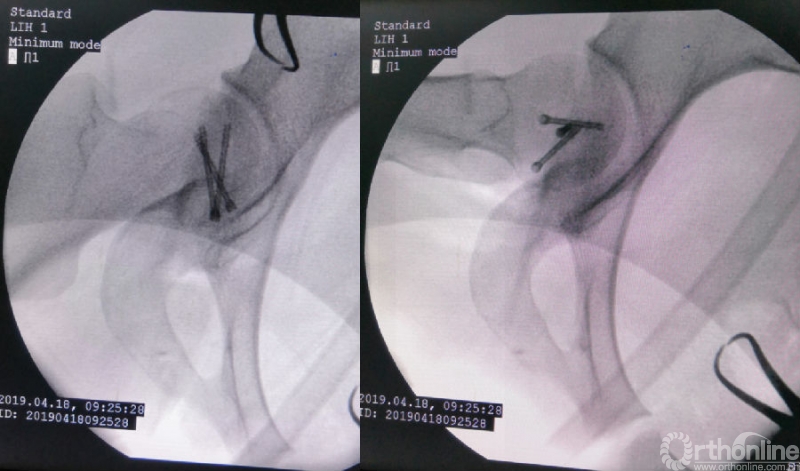

术中资料

对横跨切口远端的旋股内侧动脉血管束应特别注意,其自股骨颈的前方经内侧绕至后方延伸为旋股内侧动脉深支,是股骨头血供的主要来源。

术后影像学资料